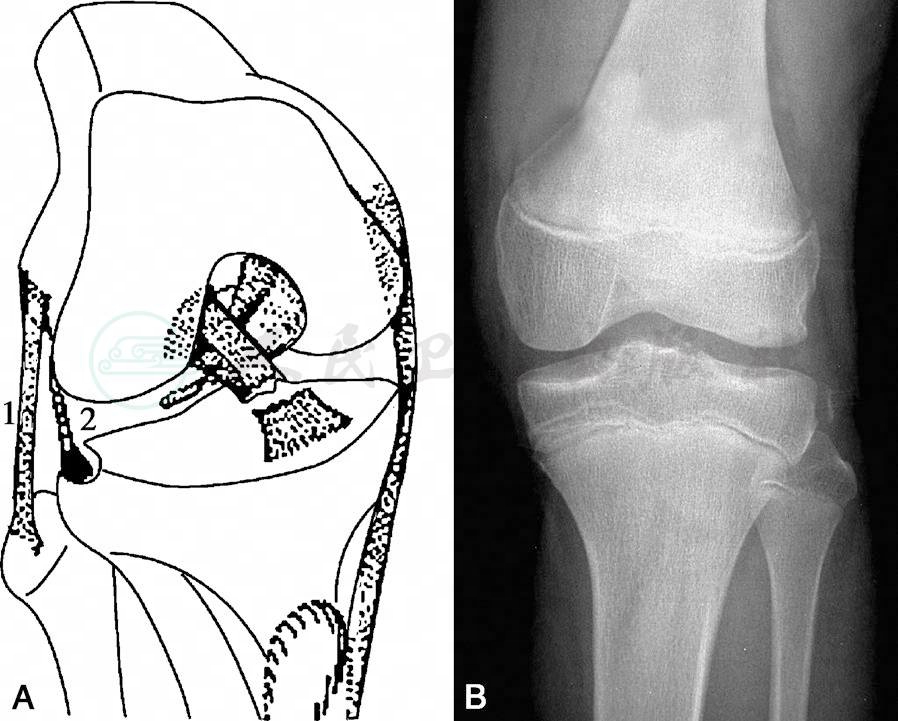

在此还需注意一特殊意义的骨折:Segond骨折,是指胫骨平台外侧的撕脱骨折,也称外侧关节囊征,经常出现在新鲜的膝关节损伤中(图7A)。撕脱的骨片是与外侧关节囊的中央部分或外侧半月板胫骨韧带相连,骨片的形状多为椭圆形,X线表现骨片距关节水平平均为4mm(图7B)。

图7Segond骨折

A.1.腓侧副韧带;2.外侧关节囊韧带撕脱骨折。B.X线片

Segond骨折是一个重要的放射学征象,它出现时几乎都伴随着前十字韧带的损伤。文献报道,Segond骨折合并前交叉韧带损伤的发生率为75%~100%。北京积水潭医院回顾了2000—2005年间510例前交叉韧带损伤的病例,Segond骨折发生率为7.6%,Segond骨折合并前交叉韧带损伤的发生率为95.1%。